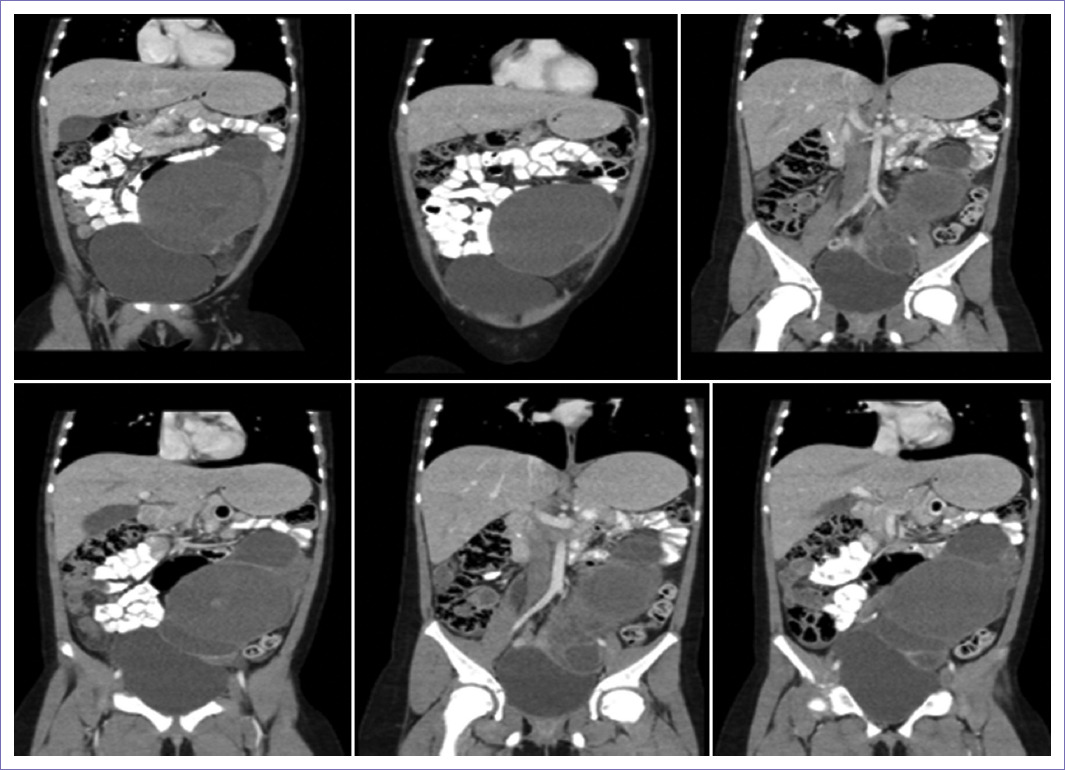

Se presenta el caso de una paciente de nueve años con cuadro de siete meses de evolución de masa abdominal, dolor abdominal intermitente y polaquiuria. Al examen físico se palpa masa lobulada en hemiabdomen inferior, predominantemente izquierdo, dura, con tamaño aproximado de 20 x 10 cm. Reporte de ecografía de abdomen con evidencia de ovario derecho de 153 x 89 x 89.6 mm para un volumen de 640 cc en su interior con quiste complejo multilocular de 146 x 76.9 mm con una formación sólida en su interior de 18.9 x 7 mm con un tabique de 3.3 mm con vascularización periférica en su interior. Se solicitó tomografía computarizada (TC) de abdomen contrastado (Fig. 1), encontrando masa multilobulada multiseptada con calcificaciones, nódulos sólidos murales dependientes de los septos y paredes, contenido heterogéneo de predominio hipodenso que ocupa parte del flanco y fosa ilíaca izquierdas rechazando las asas intestinales y el fondo de la vejiga urinaria, ejerciendo efecto compresivo sobre el uréter izquierdo con dilatación pieloureteral grado I, masa que mide 160 x 90 x 95 mm y de probable origen anexial. Marcadores tumorales con CA125 elevada en 1,260, hormona gonadotropina coriónica humana fracción beta (b-HCG), antígeno carcinoembrionario y alfafetoproteína (AFP) en rango normal.

Figura 1 Tomografía computarizada de abdomen. Masa multilobulada multiseptada con calcificaciones puntiformes periféricas en su interior, nódulos sólidos murales dependientes de los septos y paredes, contenido heterogéneo de predominio hipodenso que ocupa parte del flanco y fosa ilíaca izquierdas, de probable origen anexial izquierdo.